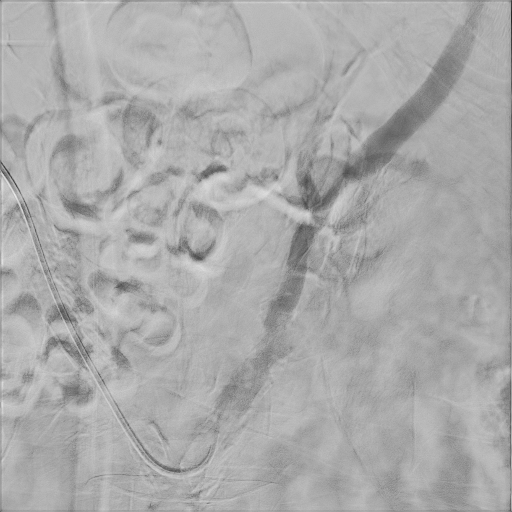

Peripheral angiogram showed diffuse atherosclerosis and multiple critical stenosis of bilateral ATK artery. Considering the patient's chief complaint was right leg tenderness, PTA for right leg was performed.

Owning to multiple stenosis and total occlusion, terumo wire cannot pass through the lesion. we ever use Connect wire, V-18 wire and even shift to Astato for calcified lesion with the assist of CXI. After several times attempt of antegrade wiring, the V-18 wire finally pentrate thrthrough the calcified lesion and advanced to distal popliteal artery. Finally the V-18 wire pass the lesion and balloon angioplasty was performed. Diffuse dissection with TIMI II flow was discovered after balloon angioplasty, thus we deployed Supera stent at SFA.Final angiogram showed acceptable result.